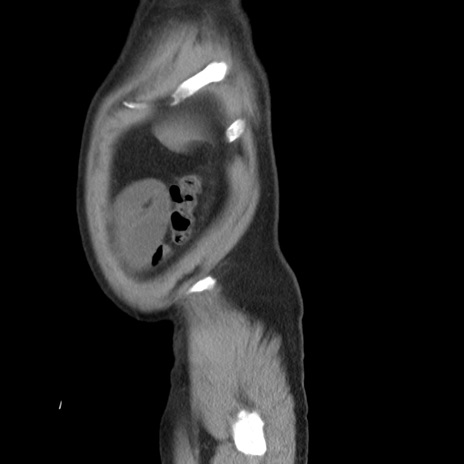

横断像

【症例】 60歳代男性

【主訴】 腹部膨満、嘔吐

【現病歴】5日前頃より倦怠感を認め食事量減少し4日前の朝嘔吐、食事摂取困難となった。 3日前近医受診し点滴施行され整腸剤などを処方された。 当日他院を受診し、腹部膨満著明、炎症反応の上昇(CRP10.8、WBC11200)あり、紹介受診となる。

【身体所見】 意識JCS1 受け答えがはっきりしないBP 111/57mHg、 P 67bpm、、BT35.2°C、SpO2 97%(RA)、 腹部:膨隆、打診で鼓音あり、全体的に圧痛有り、腸蠕動音(-)、反跳痛ははっきりせず。

【データ】WBC 11400、CRP 14.20